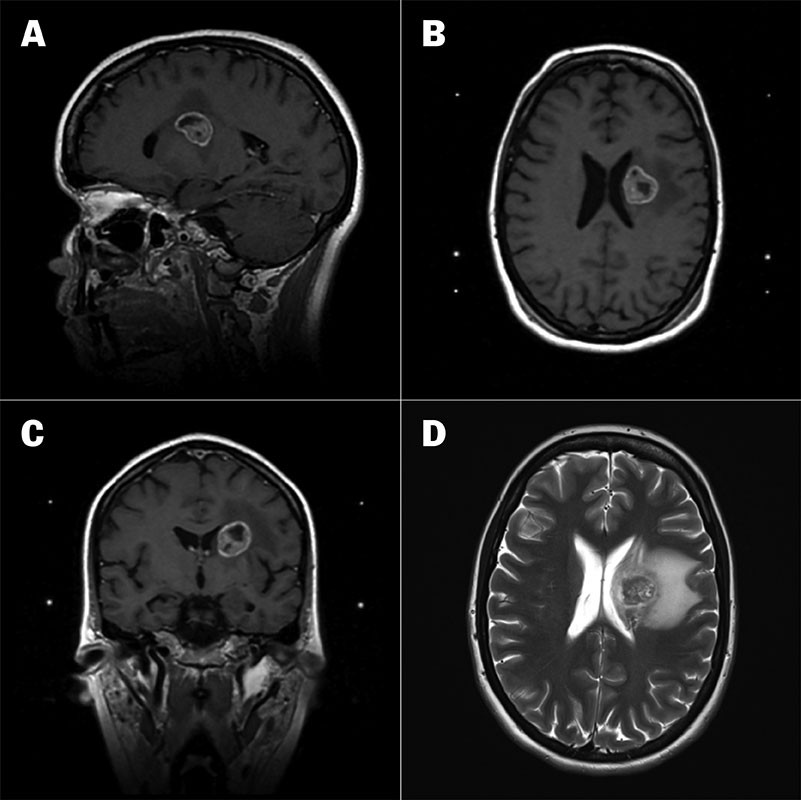

Brain CT and MRI revealed a 23 mm large expansive process and perifocal oedema in the left thalamus, exerting a mass effect on the adjacent left lateral ventricle (Figures 1a–d). A chest CT revealed a 5.6 cm tumour in the right upper lobe (Figure 2). Enlarged mediastinal paratracheal lymph nodes were observed on the right side (station 4R) in addition to enlarged paraaortic lymph nodes (station 6R).